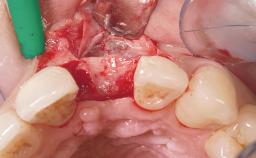

Immediate Flapless Placement of an Implant in a Maxillary Right Lateral Incisor Site

This 43-year-old male patient, a non-smoker, came to our practice because of a fracture of tooth 12 caused by a bicycle accident. Due to the combined para- and infrabony crown and root fracture, tooth extraction, and subsequent implant placement were suggested to the patient as the therapy of choice. The patient had high esthetic expectations with regard to the treatment outcome and asked for an immediate fixed provisional restoration. His individual esthetic risk profile summed up to a medium esthetic risk.

| Placement Protocol | Immediate implant placement |

| Bone Volume | Sufficient, with intact walls |